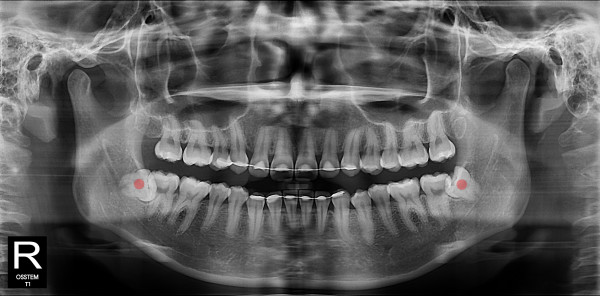

사랑니발치 10대/여성

ae27575af29d49719312fde5a1f0cca6_1764402130_3732.jpg